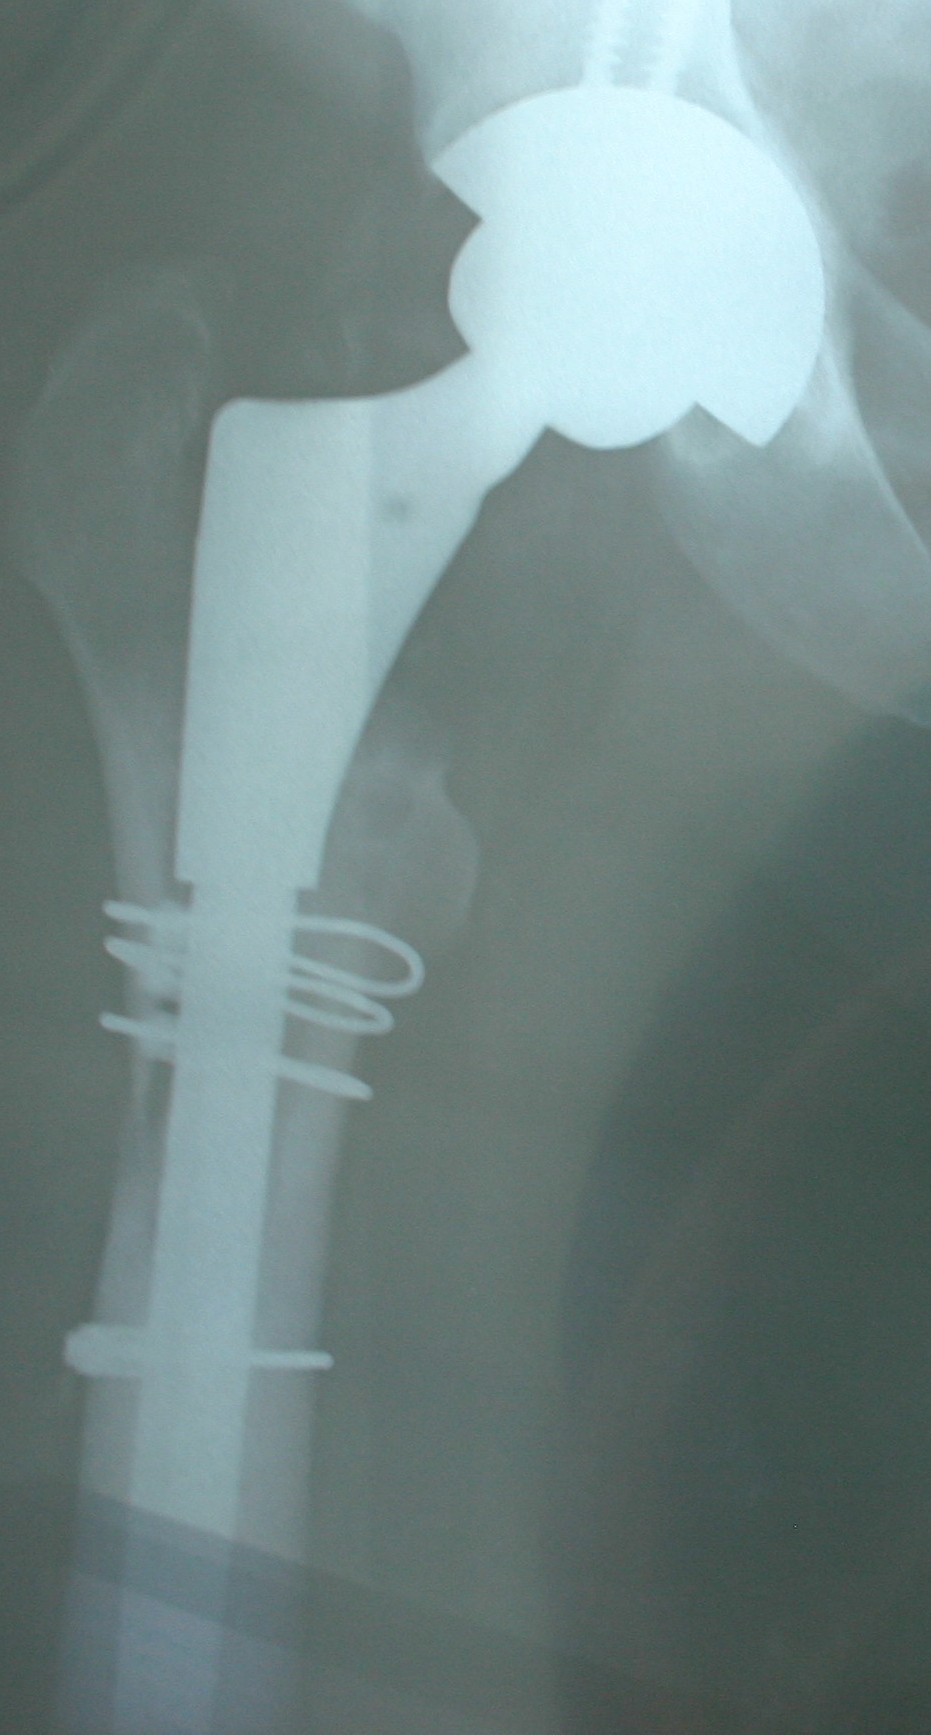

Here are the X-Rays of the revised hip – wired for everything except Digital FM, it seems!

- Split the femur to remove the previous Birmingham Spectron (S&N) femoral implant and remove excess glue and metallosis gunk.

- Bone graft to fill voids – wired femur back together to give bone strength while it heals – the fourth wire is to strengthen the mid femur because the new implant has a longer stem.

- New stem is press-fit.

- Then remove old acetabular cup – bone graft to fill out the void left – new cup put in and a couple of screws to make sure everything stays in place.

- Femoral head and cup are now inserted – ceramic on ceramic.

- The revision system is by Zimmer.

- To the right you can see the 38 or so stainless steel staples used to close the wound – removed on day 12 with only a few stings – no drama.

- The quality is not very good – taken on day one with me lying on a normal hospital bed and a very creative X-Ray team finding ways to get the required shots without moving me, the pain pump and the two drips too much – a real plumber’s muddle!

- Next week before I see the surgeon I will get a new set of X-Rays which should be a little crisper!